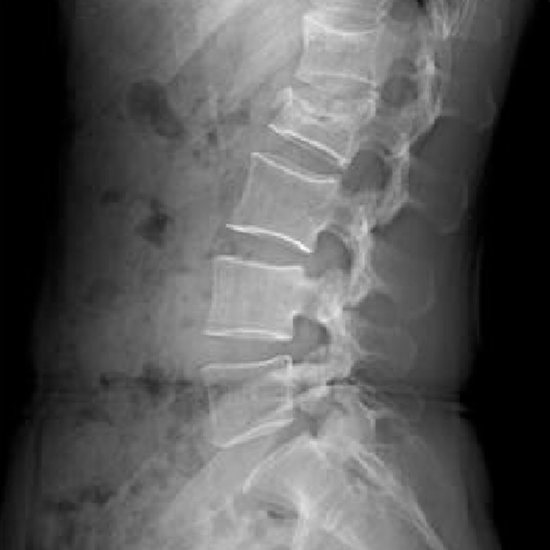

What is an X-ray Lumbar Spine Lateral View Test?

The lateral view is obtained from the side of the patient. It identifies persistent back pain, diseases, infections, slipped discs, tumors, osteoporosis, and osteoarthritis. It helps analyze birth defect-related aberrant spine curvature.